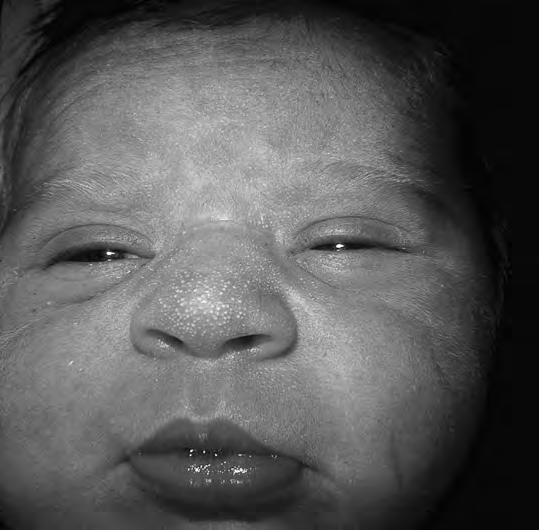

Características de la piel

En la cara (zona de la raíz de la nariz, párpados y frente) y a veces en el occipucio, son frecuentes pequeñas dilataciones telangiectásicas (angiomas capilares o planos) denominadas nevi materni. Suelen enrojecer al llorar el niño y palidecer progresivamente, hasta desaparecer hacia el final del primer año. Es frecuente encontrar, sobre todo en las alas de la nariz, unos elementos puntiformes y amarillentos, como pequeños quistes sebáceos (millium facial) (Fig. 2.1.2) que desaparecen espontáneamente al segundo o tercer mes. Asimismo, a menudo aparecen a los pocos días de vida lesiones puntiformes de acné neonatorum, relacionadas con la crisis hormonal. Las lesiones son mayores y más dispersas que, en el caso del millium, tienen ligera reacción inflamatoria y curan en el plazo medio de 8-10 días. En la región sacra y nalgas existe, a veces, una mancha de color pizarroso que puede llegar a ser muy extensa, que desaparece a menudo hacia el primer año pero que en el lactante puede llevar a la confusión con hematomas: es la mancha de Baltz y, en general, está en relación con la pigmentación racial de la piel. Si se detectan manchas de color café con leche harán sospechar una neurofibromatosis, cuando aparecen más de tres a esta edad. En algunos casos pueden surgir ampollas de succión en manos o pies por succión bucal en el periodo fetal; en muchos casos se observa la ampolla rota y queda la lesión residual redondeada. Las manchas acrómicas son sugestivas de esclerosis tuberosa.